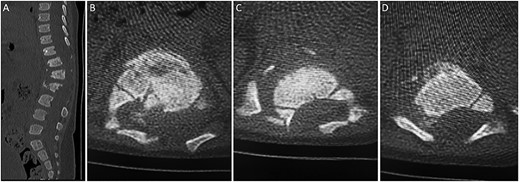

The decision was to perform posterior thoracolumbar instrumentation. The risks and possible complications of the surgery were explained to the family. The aim of the surgery was to correct the kyphotic deformity and facilitate the rehabilitation and nursing course. Posterior thoracolumbar instrumentation using the posterior cervical fixation set was successfully performed (Fig. 4A and B). In the surgery, the facet joint was preserved to prevent fusion and long-term sequelae such as crankshaft deformity. The patient recovered well with no complications after the surgery and was discharged home on a TLSO brace.

(A–B) Spine radiograph demonstrating bilateral paraspinal rods spanning from the level of T10 to L3 transfixed with pedicular screws. The screws and rods are in situ with signs of healed fracture. (C–D) Interval removal of the hardware transfixing the compression fractures of the lower thoracic and upper lumbar vertebrae. (E) Axial CT scan 7 months postoperatively confirming fusion.

Outcome and follow-up

Seven months after the surgery, a follow-up CT and plain radiograph showed healing of the fracture and excellent alignment. The hardware of the posterior thoracolumbar fixation was removed to prevent scoliosis and crankshaft deformity (Fig. 4C–E). The patient tolerated the procedure well and was discharged with regular clinical and radiological follow-up in the pediatric neurosurgery clinic. Her neurological status remained unchanged, i.e. ASIA A.